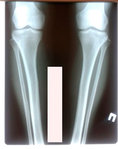

Исходник - 48 лет.

Диагноз: варусная формация голеней.

Дата операции - 17.10.2019г.